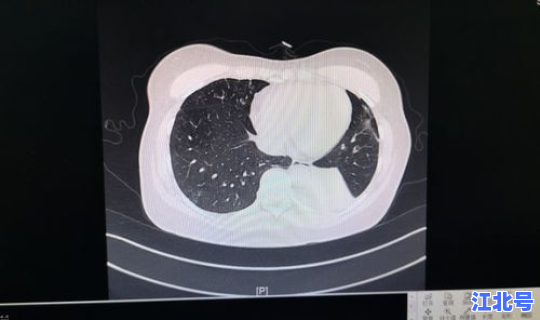

随着症状的加重,病人会出现呼吸困难 、胸闷、气短,甚至会出现呼吸窘迫等严重症状。进行影像学的检查会发现肺部有磨玻璃一样的肺间质的改变。表现严重的还会出现脓毒血症、感染性休克 、凝血功能障碍和肾功能衰竭等 。